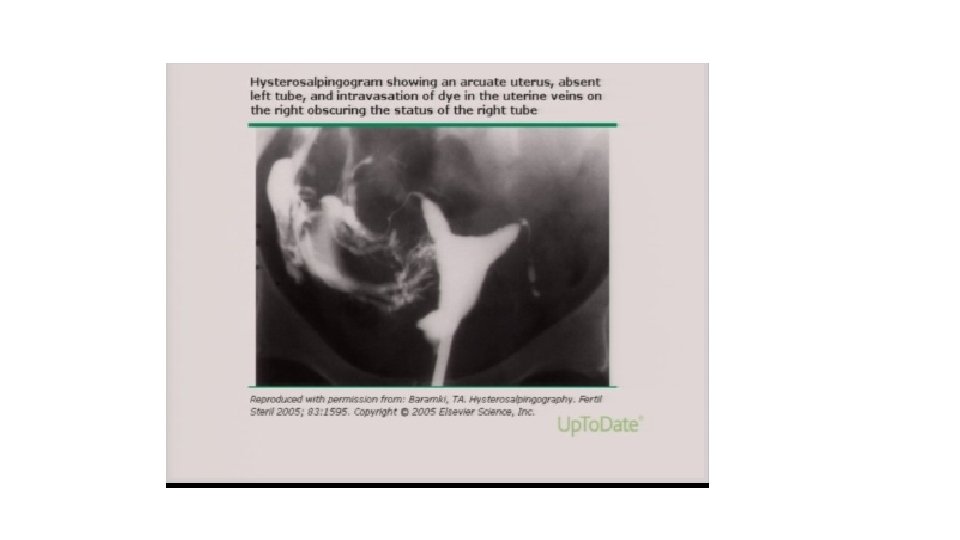

Histerosalpingografi (HSG) • Mensin bitiminden hemen sonra 2– 5. gün içinde yapılmalıdır (HSG’de distal tubal obstrüksiyon gösterildiğinde doksisiklin 5 gün boyunca günde iki kez 100 mg endikedir) • • Suda ve ya yağda çözünen kontrast madde kullanılarak yapılır Terapötik etkisi olabilir HSG nin PPD; %38 NPD; %94 tür Proksimal ve distal obstriksiyonları gösterebilir • Öncü • İlk film - uterin konturları ve tubal geçirgenliği değerlendirir • Post-değerlendirme filmi - kontrast lokülasyonunun olduğu bölgeleri saptamak için